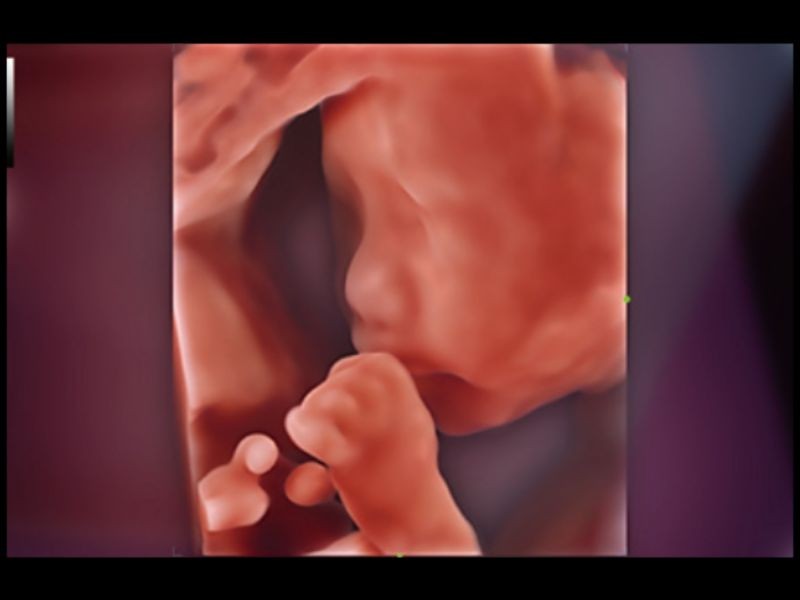

Rosto Inteligente

Remoção automática de oclusões sobre a face fetal com um clique

OB inteligente

Medição automática de biometria fetal

Aviões inteligentes CNS

Reconhecimento automático e medição do sistema nervoso central fetal